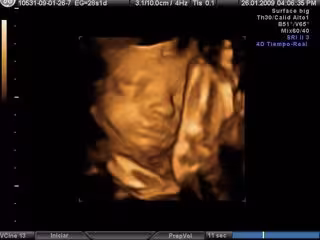

Archivo - Ecografía en 3D- embarazo

Archivo - Ecografía en 3D- embarazo - EUROPA PRESS - Archivo